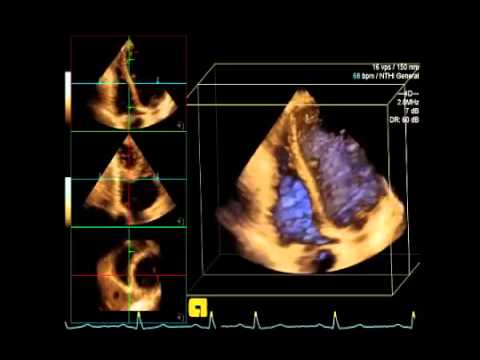

Realizamos ecocardiografía fetal, de forma exclusiva utilizamos la tecnología 3D/4D de alta definición, que permite diagnósticos cardiológicos de precisión inigualable.

ECOCARDIOGRAFIA 3D 4D

Una innovación del examen 2D donde se obtiene imágenes tridimensionales del corazón del bebe.